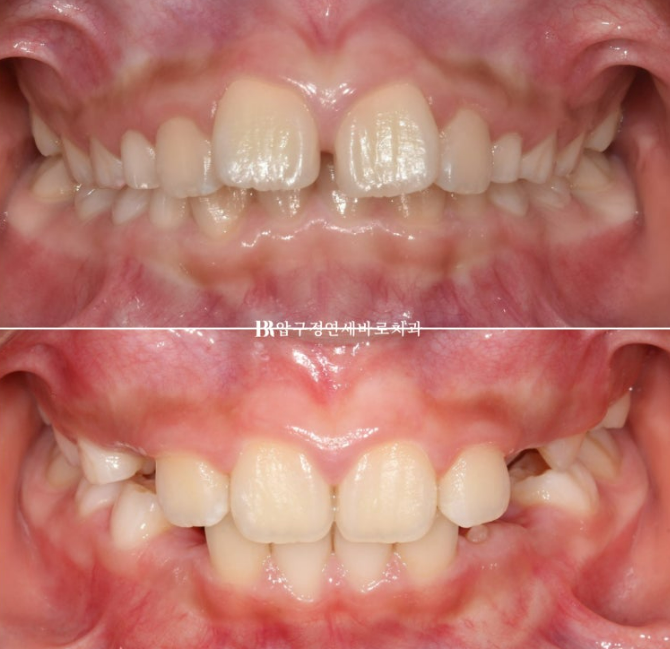

23.04

가장 먼저 보이는 것은 앞니 사이가 벌어진 것 이지만

이 벌어짐은 송곳니가 나오면서 모이기도 하기 때문에 큰 문제는 아닙니다.

그보다는 윗니가 아랫니를 많이 덮어 아랫니가 잘 보이지 않습니다.

과개교합 이라고 합니다.

윗니 아랫니 중심선이 맞지 않는 중심선 불일치도 보입니다.

옆에서 보시면 윗니 돌출이 심해보입니다.

하지만 골격 분석을 해보면 아래턱이 작아서 그렇게 보이는 것 입니다.

23.09

맞아진 위 아래 앞니 중심선과 개선된 과개교합

돌출된 앞니도 제자리로 들어갔습니다.

이제 치료 전 후 비교 보겠습니다.

총 치료 기간은 22개월 입니다.

23.04~25.01

가지런해진 앞니와 영구치를 위한 충분한 공간

윗니 돌출이 많이 개선이 되었습니다.

튀어나온 윗니가 뒤로 들어갔나? 싶겠지만 사실은 위니가 뒤로 들어간 것이 아니라

아랫니를 품은 아래턱뼈가 성장하여 앞으로 나온 것 입니다.